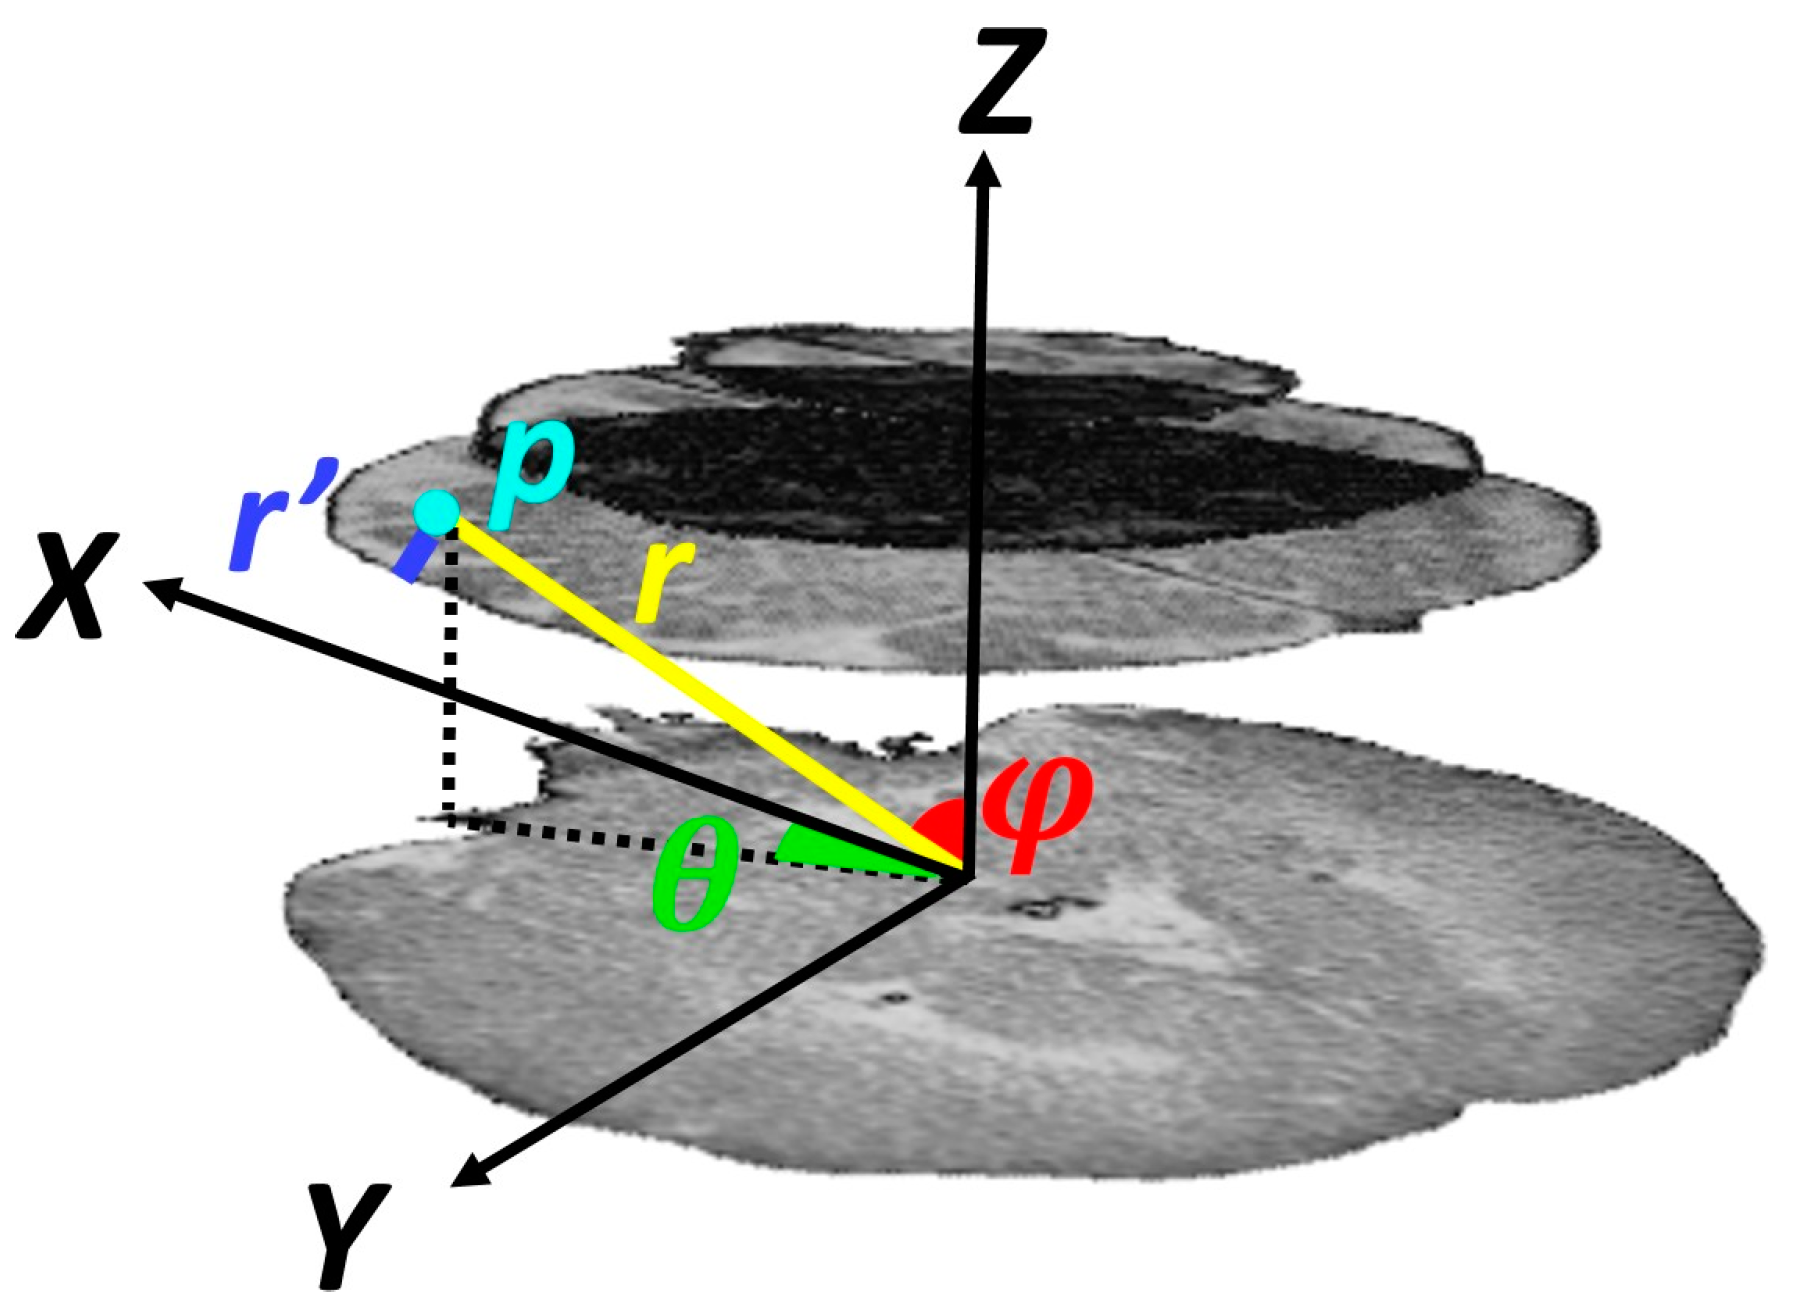

Location-Based Features

As mentioned above, subdural hematomas are more likely to occur in specific regions. Thus, location information was incorporated into our model by extracting features in a spherical coordinate system. These parameters are radial distance, azimuth angle, and elevation angle. The origin was fixed on the center of the mass of the skull on the lowest selected slice. As shown in

Figure 4, the elevation angle,

φ, determines the angle between the horizontal plane and the line connecting the point to the origin. The azimuth angle,

θ, corresponds to the angle between the projection of the line connecting the point to the origin on the horizontal plane and the brain midline that separates it into two hemispheres. The radial distance,

r, measures the distance of the point to the origin. As proximity of a point to the skull increases the likelihood of injury, in addition to the radial distance, we considered the distance between the point and the inner surface of the skull,

r′.